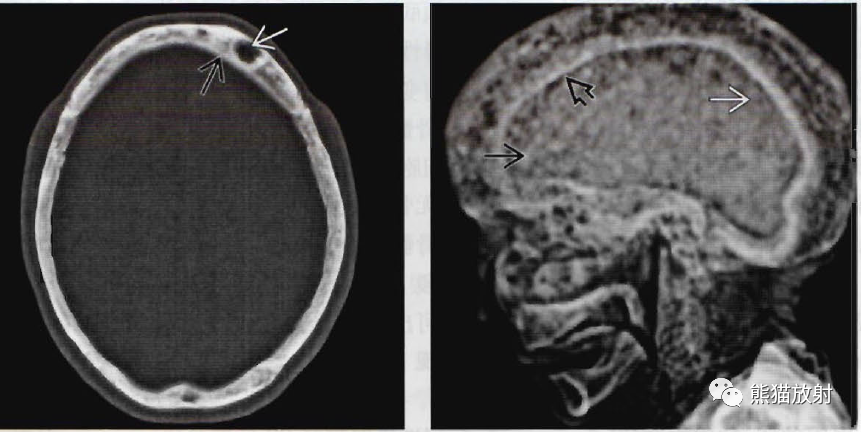

颅骨纤维结构不良,paget病丨影像诊断相关要点_医学界

paget骨病,又称畸形性骨炎或变形性骨炎,为一种罕

骨肿瘤样病变的影像学诊断之paget病与abc